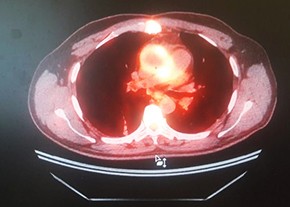

Фото носит иллюстративный характер. Из открытых источников.

ПЭТ с 18F-ФДГ: ПЭТ/КТ-картина в пользу протезного эндокардита аортального клапана.